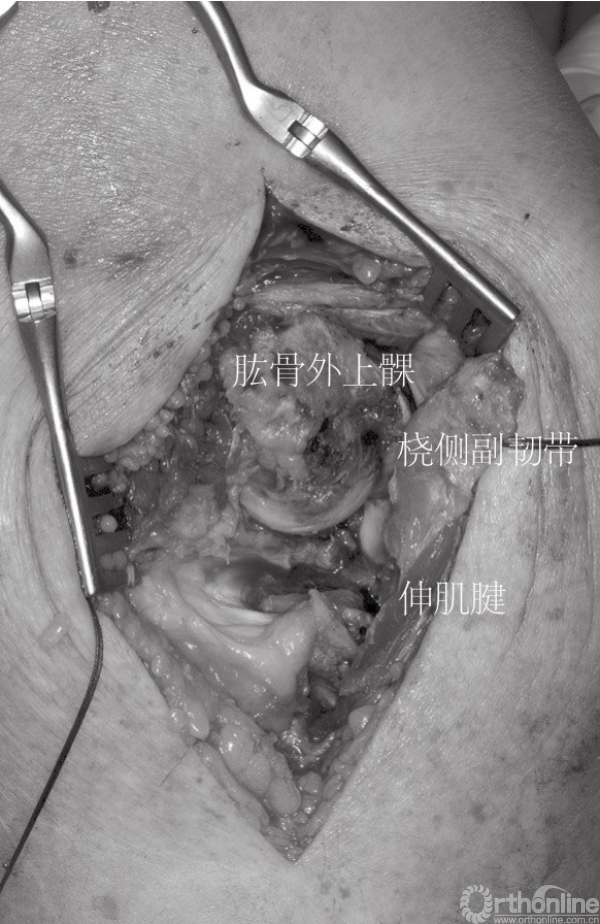

如果冠状突骨折块足够大,从外侧入路可以直接观察到,尤其是通过桡骨头的缺损处或者在桡骨头切除后。因此,在复位桡骨头之前先处理冠状突骨折,冠状突骨折块可以通过牙科刮匙进行复位和维持,然后经皮从尺骨背侧面置入空心螺钉进行固定。如果外侧入路进行固定存在困难,可以考虑直接由内侧入路进行暴露。小的游离骨折块可以去除(图4),套锁缝合前关节囊至尺骨可以加大稳定性(图5)。

图4 该损伤出现关节囊、桡侧副韧带及外侧肌肉软组织损伤(⋆桡骨头切除后)